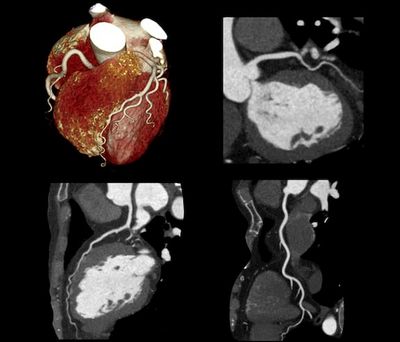

КТ стали важливим інструментом моніторингу ефективності лікування захворювань. КТ може допомогти медичним працівникам визначити, чи працює лікування, візуалізуючи зміни у внутрішніх структурах організму. Наприклад, якщо пацієнт проходить хіміотерапію для лікування раку, КТ можна використовувати для моніторингу розміру пухлини. Якщо пухлина зменшується, це означає, що лікування працює.

КТ-сканування використовують для оцінки лікування захворювань у різних медичних станах. Деякі з найпоширеніших захворювань, при яких використовується КТ, включають рак, серцево-судинні захворювання та неврологічні розлади. КТ може допомогти медичним працівникам визначити ефективність хіміотерапії або променевої терапії для лікування раку. Вони також можуть використовуватися для моніторингу прогресування серцево-судинних захворювань або ефективності лікування неврологічних розладів.